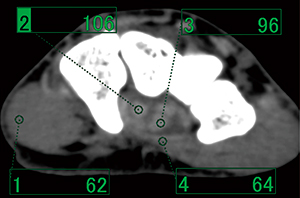

VR画像での腱・靭帯の描出を目的としたCT撮影を行う場合,画像ノイズの少ない画像を得ることが重要である。通常,骨・関節の診断を目的とした場合は120kV,30~60mAs程度で撮影を行っているが,腱・靭帯描出を目的とした場合は100~200mAsまで線量を上げて画像ノイズを少なくする必要がある(図1)。

また,135kVの高管電圧を使用すると,FOV中心付近にある腱・靭帯のCT値低下に比べて周囲の筋肉のCT値低下が大きくなるため,相対的にコントラストを上昇できる。検査部位にもよるが,VR画像を作成する上で腱・靭帯と筋肉の分離がしやすくなる(図2,3)。

図1 撮影条件と手指屈筋腱の描出能の差異

骨のVR画像であれば30mAsで十分に作成可能であるが,腱の描出は難しいため線量を上げる必要がある。

図2 120kVにおける屈筋腱と周囲組織のCT値 |

図3 135kVにおける屈筋腱と周囲組織のCT値 |